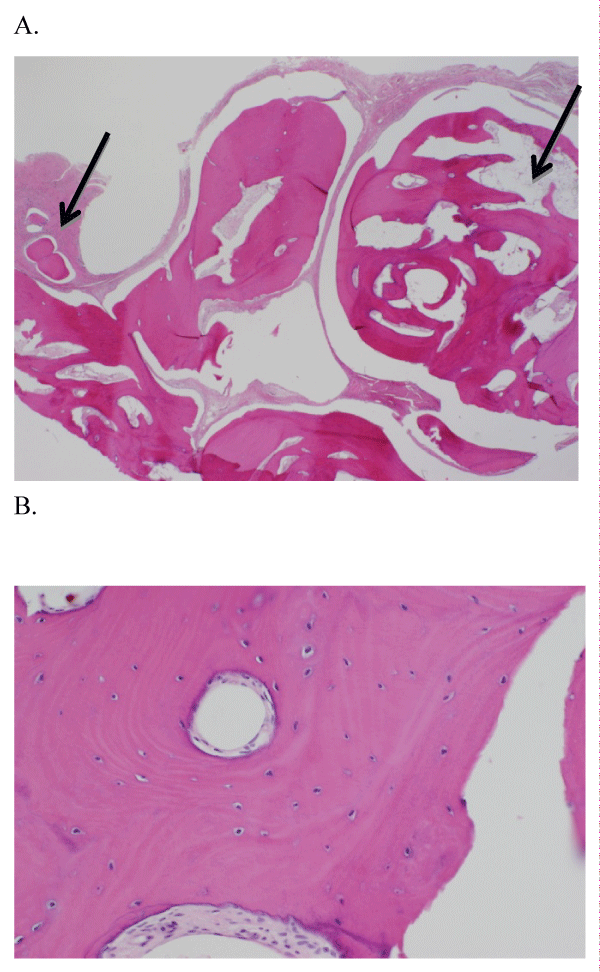

Clinical examination revealed no cervical lymphadenopathy and neurologic examination was normal, with no paresthesia in the left lower lip. The patient did have a firm, non-mobile, and non-tender 1.5 cm diameter nodule adjacent to the buccal cortex and apical to teeth 3.4 and 3.5. The mucosa overlying the nodule appeared normal, and there were no signs or symptoms of an infection. The mass was imaged initially with a panoramic and occlusal radiograph, the occlusal radiograph showed a calcified mass that was not continuous with the lateral cortex of the mandible. A computed tomography (CT) scan was performed and showed an ovoid density projecting superficial to the left mandible, adjacent to the mental foramen (Figure 1). A plane of fat existed between the nodule and the adjacent mandible, and the overlying muscle was displaced laterally. The nodule was measured to be a maximum of 2.0cm in diameter. There was also no soft-tissue component to the lesion. The patient was also sent for blood work at that time, with no abnormalities noted: calcium level was 2.51mmol/L (normal 2.23-2.58mmol/L), phosphorus level was 1.18mmol/L (normal 0.76-1.53mmol/L), and white blood cell (WBC) count was 9.8 WBC/μL (normal 4.5-11 WBC/μL).

Figure 1: Axial CT image and Coronal CT